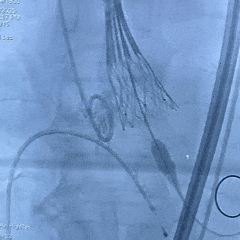

手术过程

左侧冠脉造影

右侧冠脉造影并行PCI

根部造影

可见瓣叶钙化,伴反流

TF21瓣膜0位初始释放

全展开后多角度根部造影:瓣膜深度形态合适,冠脉灌注良好,少量瓣周漏,选择解锁脱钩

脱钩后造影评估:瓣膜深度可,展开良好,少量瓣周漏

外周造影检查,血管无损伤